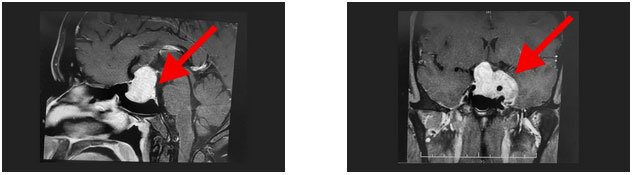

鞍区MRI平扫+增强显示:蝶鞍扩大,鞍底骨质下陷,鞍内垂体上缘隆起,鞍隔处见“腰症”;增强扫描,病变早期和延迟期持续强化,最大层面约4.5*3.7*3cm;鞍上视交叉受压上抬,左侧海绵窦及左侧颈内动脉受包绕。检查催乳素超3000μIU/mL,远超正常值。

神经外科6B病区潘仁龙主任、李士其教授、吴治群博士会诊后考虑为侵袭性泌乳素型垂体巨大腺瘤,正是垂体瘤导致小刘性功能下降,并且肿瘤已经压迫视神经导致视力下降,手术指征明确。

▲ 影像显示垂体占位,侵及左侧海绵窦